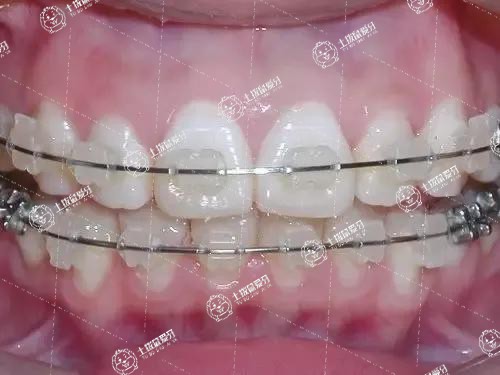

我們?cè)谌粘I町?dāng)中看到一些朋友有牙齒排列不整齊的話(huà),有的父母也會(huì)有牙齒畸形,那么,很明顯,這屬于遺傳因素。在臨床上牙齒畸形是否遺傳都可以進(jìn)行牙齒矯正的。不過(guò),也有人會(huì)擔(dān)心牙齒矯正會(huì)反彈,當(dāng)然,在門(mén)診中確實(shí)有反彈的幾率。牙齒矯正后會(huì)反彈到什么程度?對(duì)此,接下來(lái),我們一起來(lái)了解一下。

牙齒矯正后通常不會(huì)反彈到跟原來(lái)一樣的,具體需要根據(jù)牙齒矯正后恢復(fù)情況以及日常生活習(xí)慣決定的。最好選擇正規(guī)的醫(yī)院進(jìn)行治療,如果不及時(shí)改正不良的口腔習(xí)慣,可能會(huì)出現(xiàn)牙齒矯正反彈情況。通常在牙齒矯正后飲食以清淡軟流質(zhì)類(lèi)食物為主,不可以吃太辣或者過(guò)于堅(jiān)硬類(lèi)食物,以免對(duì)牙齒矯正造成不良影響。

牙齒矯正是會(huì)反彈的,因?yàn)檠例X矯正以后需要戴保持器,如果保持器沒(méi)有戴好,保持器的前兩年沒(méi)有配合使用,白天晚上并沒(méi)有都戴,這樣牙齒就會(huì)容易反彈。

如果真的反彈了,只有一個(gè)選擇就是重新矯正,重新矯正跟最開(kāi)始的矯正是差不多的,但是矯正的時(shí)間會(huì)相對(duì)比原來(lái)要短一些,因?yàn)榉磸椀某潭炔粫?huì)很厲害,所以重新矯正的時(shí)間可能在半年到一年的時(shí)間就可以了,不過(guò)之后還是要記的一定要好好戴保持器,這是非常至關(guān)重要的。

牙齒矯正后反彈,若反彈程度較輕,可以佩戴保持器控制其進(jìn)一步反彈,若反彈程度較重,可進(jìn)行二次矯正,具體如下。

牙齒矯正后會(huì)反彈到什么程度

1.佩戴保持器:正畸治療后可能因?yàn)檠啦酃歉慕ㄉ形赐瓿傻仍?,造成輕微反彈,一般對(duì)全口的咬合關(guān)系及美觀(guān)無(wú)影響,需要佩戴保持器至牙槽骨改建完成,防止其進(jìn)一步反彈。

2.二次矯正:若反彈程度較重,造成咬合關(guān)系紊亂、影響美觀(guān)、咬頰咬舌等癥狀,需要再次佩戴矯治器進(jìn)行二次矯正。

建議前往正規(guī)醫(yī)療機(jī)構(gòu)就診,接受專(zhuān)業(yè)治療。